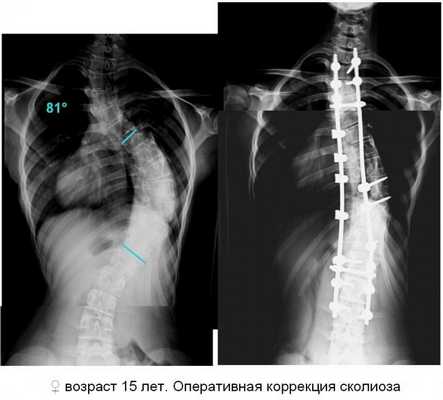

S-образный сколиоз: в грудном отделе позвоночника 4 степени, в поясничном отделе позвоночника 3 степени. Дистрофические изменения тел грудных позвонков 3 степень сколиоза. Грудной отдел

4 степень сколиоза с фиксацией металлическими стержнями Самое сильное искривление – «зашкаливающая» 4 степень

Показаниями к хирургической коррекции сколиоза у детей служат быстрое прогрессирование деформации, несмотря на проводимое консервативное лечение, угол искривления позвоночника более 40°, нарушения работы жизненно важных органов. Оптимальным периодом для оперативного лечения является возраст 10-14 лет. Операция заключается в имплантации фиксирующих устройств трансторакальным, дорсальным или комбинированным доступом. Наибольшее распространение в хирургии сколиоза получили дистракторы Казьмина, Харрингтона, эндокорректор Роднянского-Гупалова, системы Котреля-Дюбуссе и др. Перед хирургическим вмешательством проводится вытяжение позвоночника.

По показаниям могут выполняться корригирующие костно-пластические операции (клиновидная резекция позвонков), мобилизующие операции (тенолигаментокапсулотомия по Шулутко, дискэктомия), косметические вмешательства (резекция реберного горба, экстраплевральная торакопластика, резекция угла лопатки) и др. После операций проводится длительная реабилитационная терапия.

Особо сложные запущенные варианты требуют хирургического ортопедического лечения. Данный вид вмешательства употребим в ряде случаев с третьей степенью недуга и во всех с четвёртой. Если сколиоз создаёт условия для некорректной работы каких-то внутренних органов, то также показано хирургическое вмешательство. Наибольшей оптимальностью для данной операции характеризуются случаи, когда пациенту от 10 до 22 лет. Хирургическое вмешательство подразумевает введение в организм пациента особенных устройств-фиксаторов. Перед тем как хирургически изменять тело пациента обязательной процедурой должна быть вытяжка позвоночника. После операции начинается период адаптации к ношению имплантированных конструкций.

Если у больного диагностирован S-образный сколиоз 3 или 4 степени, то врач назначает операцию. Хирургическое лечение бывает 2 видов: этапное и одномоментное. В первом случае пациенту в ходе операции устанавливают постоянную металлическую конструкцию, фиксирующую позвонки. Лечебный эффект достигается сразу после вмешательства. В некоторых случаях возникает осложнение в виде тяжелейшей формы сколиоза. Вылечить ее довольно сложно. Во втором случае требуется несколько операций. Во время первой пациенту устанавливают временную металлическую конструкцию. В дальнейшем врачи выполняют серию операций с целью ее удлинения.